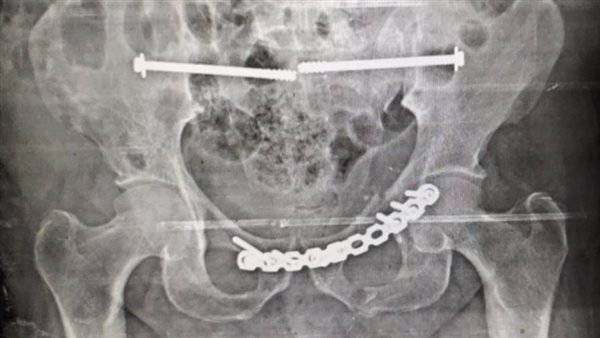

أوضح الدكتور محمد عبد الغني، مدير المستشفى، أن الجراحة أجريت بنجاح على يد فريق طبي متميز، تحت إشراف الدكتور أحمد سمير، أستاذ جراحة العظام بكلية طب قصر العيني، والدكتور محمد فرحات، رئيس قسم جراحة العظام بالمستشفى، والدكتور أنور مصطفى، أستاذ التخدير بجامعة الأزهر.

شملت العملية تركيب شرائح ومسامير وتثبيت الحوض من الخلف بالفقرات العجزية باستخدام مسامير مجوفة.